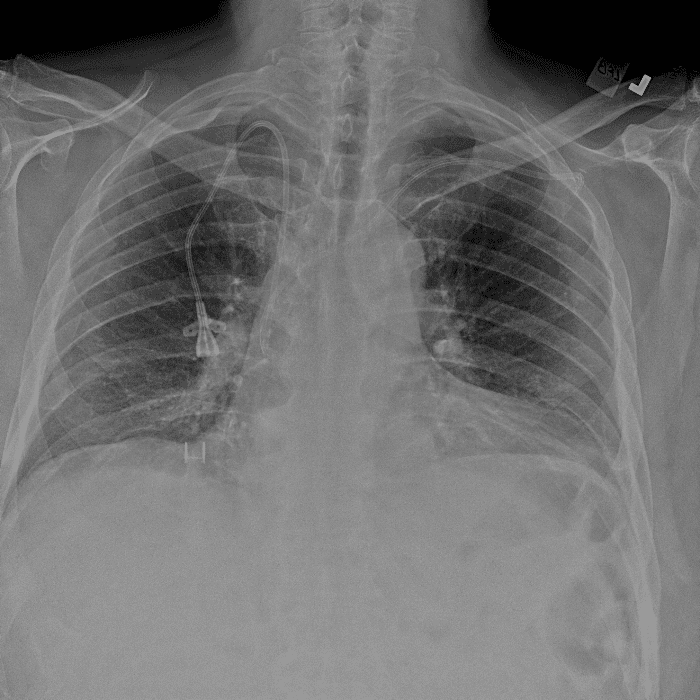

Practice Cases